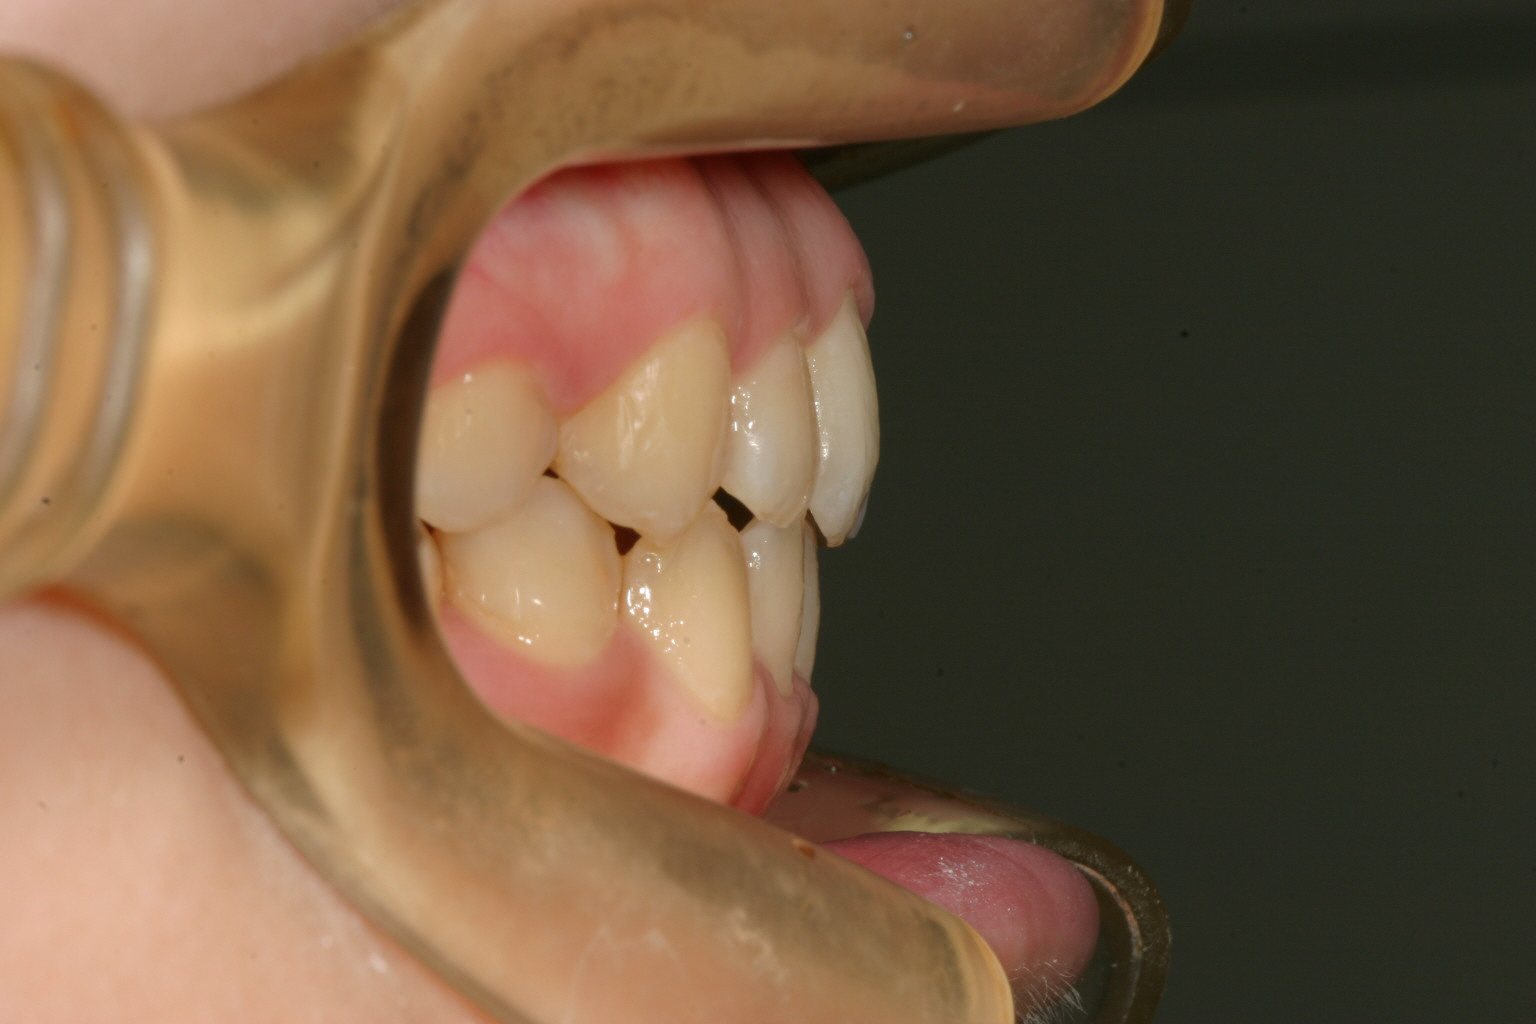

前歯に結構な叢生が見受けられます。

下顎にも上顎同様アーチがつぶれスクエアーになっています。

横から見るとオーバージェット問題無いです。